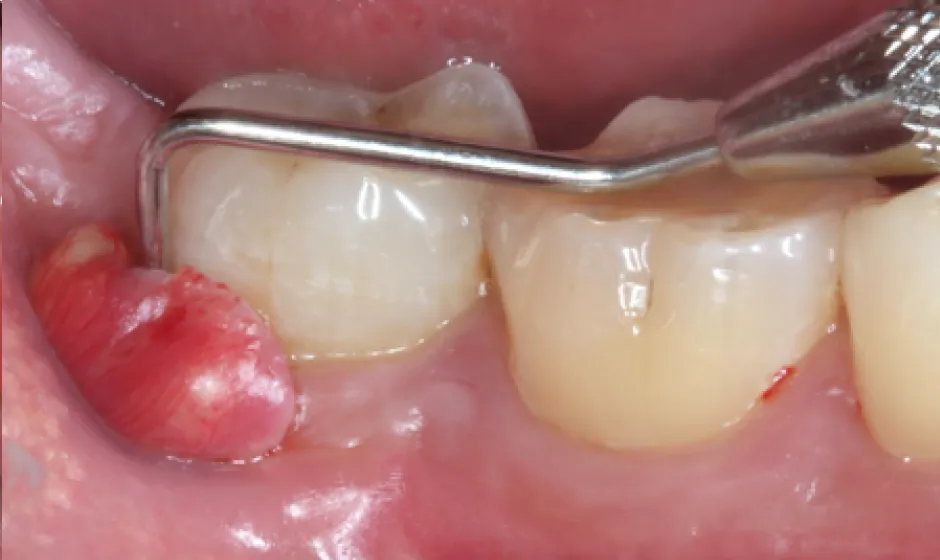

02歯周病・

重度歯周病治療歯周病は痛みが少ないまま進行し、気づいた時には歯がグラつく、膿が出る、噛みにくいといった状態になりやすい病気です。けれど、重度でも「もう無理」と決めつける前に、歯ぐき・骨・噛み合わせの状態を丁寧に評価し、今できることを一つずつ積み上げれば、守れる歯はあります。

当院では検査に基づき、基本治療から必要に応じた外科的治療や再生療法の検討まで、長期維持を見据えて段階的に進めます。津市で歯周病を本気で治したい方に、寄り添える歯科医院でありたいと考えています。症例1

- 治療名

- 【重度歯周病】歯周組織再生療法による機能回復

- 患者様

- 40代女性

- 執刀医

- Dr. 大杉

- 治療期間

- 約1年(初期治療・経過観察期間含む)

- 治療費

- 250,000円(税込)

- リスク

- 術後に一時的な腫れや痛みが生じることがあります(鎮痛剤等の処方で管理を行います)。

また、喫煙等の生活習慣によっては治癒不全のリスクが高まる場合があります。

症例2

- 【高度審美形成】歯間乳頭再建術

- 約1年

- 300,000円(税込)

- 移植組織の定着後も、メンテナンスが予後を大きく左右します。

特に歯間ブラシの不適切な使用や過度なブラッシング圧は組織の退縮を招くため、術後は当院の指導に基づいた厳密なプラークコントロールが必要です。